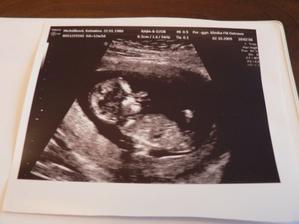

2.10.09 NT screening, krev vše je v pořádku a jsme učebnicový, taťka byl s námi na velkém UTZ 🙂